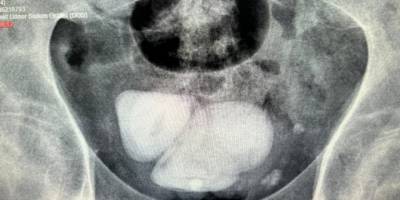

Aydın'da hastanın mesanesinden piramit şeklinde taşlar çıkarıldıAydın'da hastanın mesanesinden piramit şeklinde taşlar çıkarıldıAydın'da felçli bir hastanın mesanesinden 4 santimetre çapında biri üçgen diğerleri piramit şeklinde 4 taş çıkarıldı. Hastanın tedavi sürecini takip eden Üroloji uzmanı Op. Dr. Göksel Ayköse, AA muhabirine açıklamada bulundu.